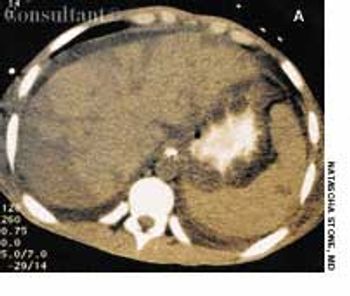

A 13-year-old girl who had leukemia presented to the emergency department with fever; chills; weight loss; fatigue; and a painful, erythematous rash with a central black lesion on the upper thigh. The patient was neutropenic and had been undergoing chemotherapy for 1 week.